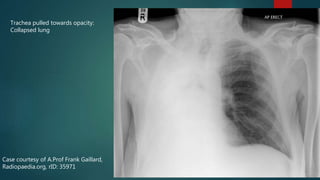

 Trachea pulled toward opacified side

Case courtesy of A.Prof Frank Gaillard,

Radiopaedia.org, rID: 35971

Trachea pulled towards opacity:

Collapsed lung

Case courtesy ofA.Prof Frank Gaillard, Radiopaedia.org, rID: 35971 Trachea pulled towards opacity: Collapsed lung